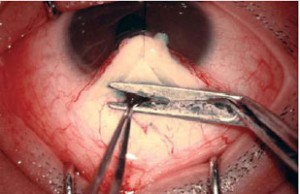

Se inscribieron en el estudio pacientes sometidos a trabeculectomía. Se midió la agudeza visual, queratometria, refractometria, y presión intraocular después de la operación, antes de la operación y a los 1, 3 y 6 meses. Los cambios en el astigmatismo se cuantificaron mediante análisis vectorial.